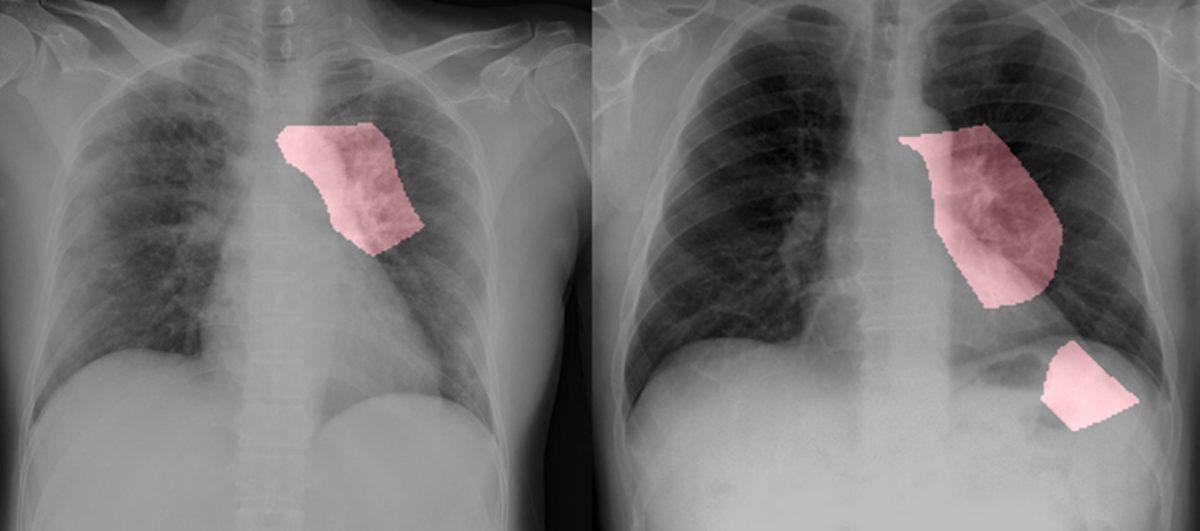

Koronavirüsün teşhisinde yapay zekanın kullanılması için çalışan Waterloo Üniversitesi’nden Linda Wang, Alexander Wong ve Kanada merkezli yapay zeka şirket DarwinAI, COVID-Net ismi verilen bir yapay zeka geliştirdiler. COVID-Net, koronavirüsüne yakalanan insanların göğüs röntgenlerinde hastalığın belirtilerini tespit edebiliyor.

COVID-Net’in geliştirilmesi için 2.839 viral ve bakteriyel enfeksiyon geçiren hastanın 5.941 röntgen görüntüsünden bir veri seti oluşturuldu. Yapay zeka, bu veri setini kullanarak koronavirüsün akciğerdeki belirtilerini tespit edebiliyor.